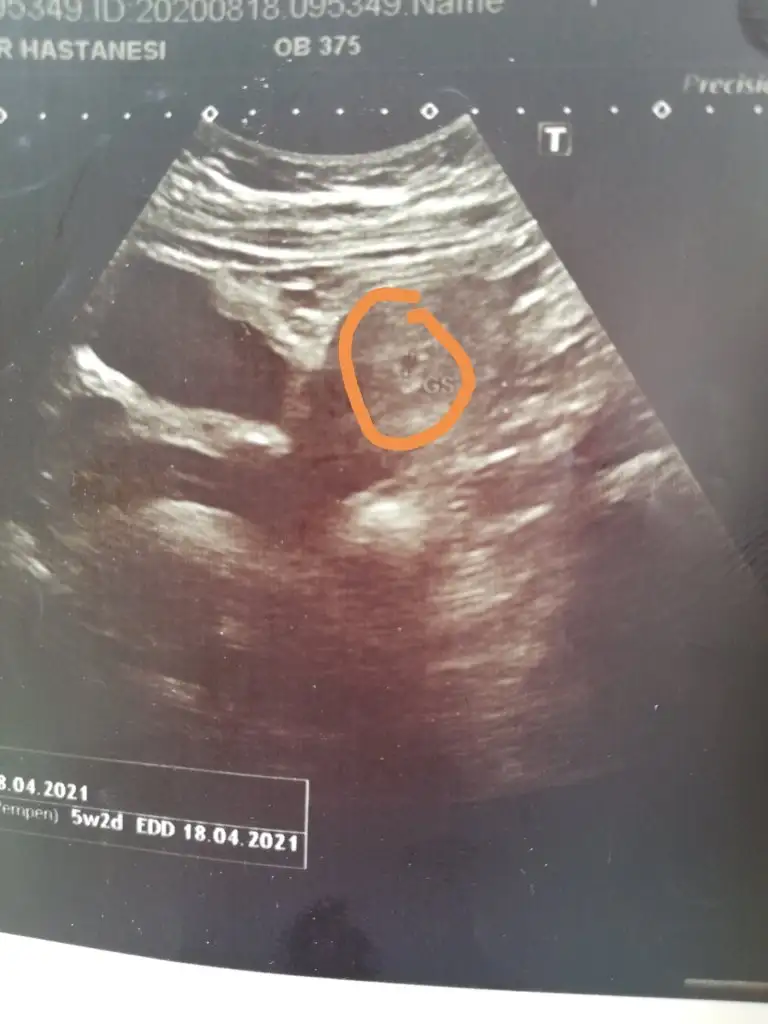

Kese daha canım haftaya oluşur daha 6-7 hafta değil cunkiKızlar selam daha bizim nubumuz falan yok. Doktor keseyi görebildiğini söyledi bebek var mı kesede ben göremedim. İşaretledipim yer kese mi yoksa bebişim mi.

Kesem neresi canım. İşaretledipim yer mi pekiKese daha canım haftaya oluşur daha 6-7 hafta değil cunki

Doktor orada bir işaretleme ölçüm gibi birşey yapmış ben orası kese mi ola diye tahmin ettim. Doğru mudurKese daha canım haftaya oluşur daha 6-7 hafta değil cunki

Evet işaretledigin yer cnmKesem neresi canım. İşaretledipim yer mi peki

Sağol canım benim bir dahakine cinsiyet yorumunu bekliyorumEvet işaretledigin yer cnm